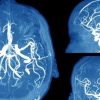

Ανεύρυσμα εγκεφάλου: Τα πρώτα συμπτώματα που δεν πρέπει να αγνοήσουμε

29 Μαΐου 2019Το ανεύρυσμα εγκεφάλου είναι η διόγκωση ενός αιμοφόρου αγγείου στον εγκέφαλο, σύμφωνα με την κλινική Mayo....